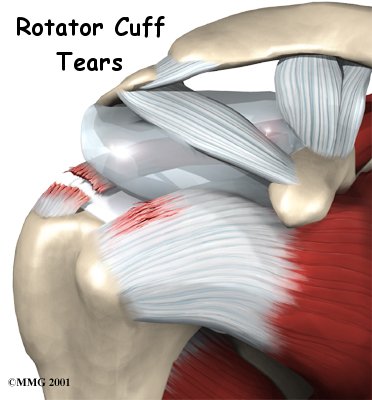

Rotator cuff tears cause pain and weakness in the affected shoulder. In some cases, a rotator cuff may tear only partially. The shoulder may be painful, but you can still move the arm in a normal range of motion. In general, the larger the tear, the more weakness it causes.

Rotator Cuff Tears

In other cases, the rotator cuff tendons completely rupture. A complete tear makes it impossible to move the arm in a normal range of motion. It is usually impossible to raise the arm away from your side by yourself.

Most rotator cuff tears cause a vague pain in the shoulder area. They may also cause a catching sensation when you move your arm. Most people say they can't sleep on the affected side due to the pain.